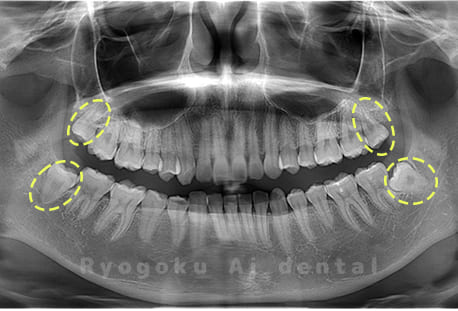

Case01

- 原因

- 水平埋伏智歯

- 治療内容

- 下顎の水平埋伏智歯を抜歯

<リスク・副作用>

手術後は痛み、腫れ、痺れなどの副作用が生じる場合があります。